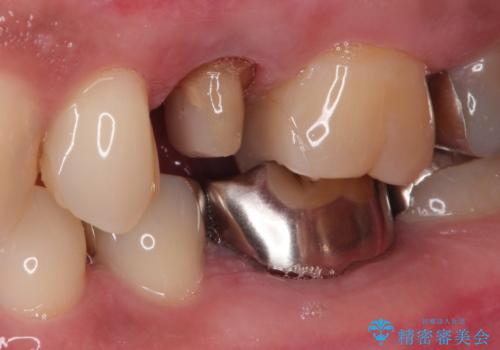

- 左上の後ろから3番目の歯のかぶせ物が適合不良であったので、根管治療を行い、オールセラミックを装着する計画としました。

またその隣の目立つ銀歯も同時に、セラミックに交換することとしました。